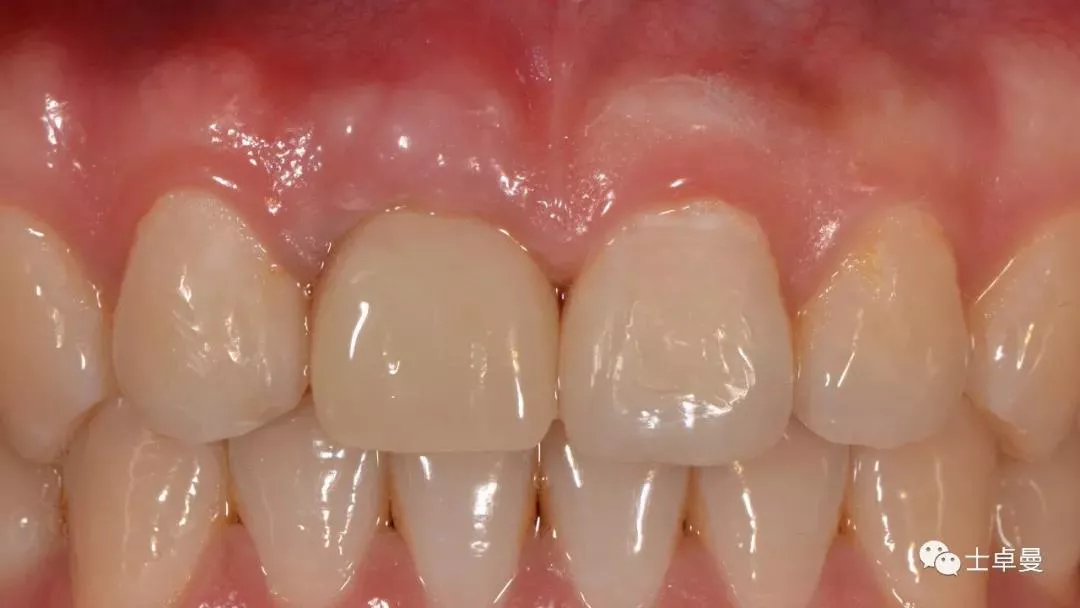

临时修复后2个月,龈缘及龈乳头位置理想,软组织健康

· 2个月后,见唇侧骨弓轮廓可,龈缘及龈乳头形态自然,去11临时修复体,植体ISQ值测定82,个性化取模,试戴Variobase氧化锆基台+LAVA氧化锆单冠,就位被动性良好,增加基台扭力至35Ncm,粘接固位上部冠,调合抛光。

完成永久修复,骨弓轮廓、龈缘及龈乳头形态自然,可见牙龈点彩,修复体外形及色泽可,患者满意。